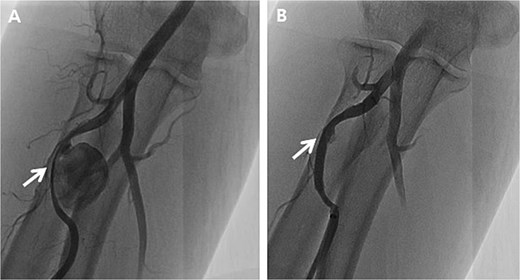

Initially, we conducted percutaneous endovascular exclusion of the proximal RAP using 3.5 × 26 mm Graftmaster covered stent (Abbott Vascular, Santa Clara, CA, USA) and observation of the distal RAP (Fig. 2). Nevertheless, no improvements were observed in the RAPs for 2 weeks after the procedure. A follow-up CT showed the distal migration of the covered stent and increased size of the RAPs. Distal lesion size increased from 0.8 cm to 1.5 cm (Fig. 3A) and the proximal lesion increased from 2.0 cm to 4.0 cm (Fig. 3B). At this point, surgery was considered suitable for the patient to achieve complete recovery.

Follow-up computed tomography of the right upper extremity, 2-weeks after the procedure. (A) Pseudoaneurysm at the distal radial artery, size increased from 0.8 cm to 1.5 cm (arrow); (B) Pseudoaneurysm at the proximal radial artery, size increased from 2.0 cm to 4.0 cm with distal migration of covered stent (arrow).